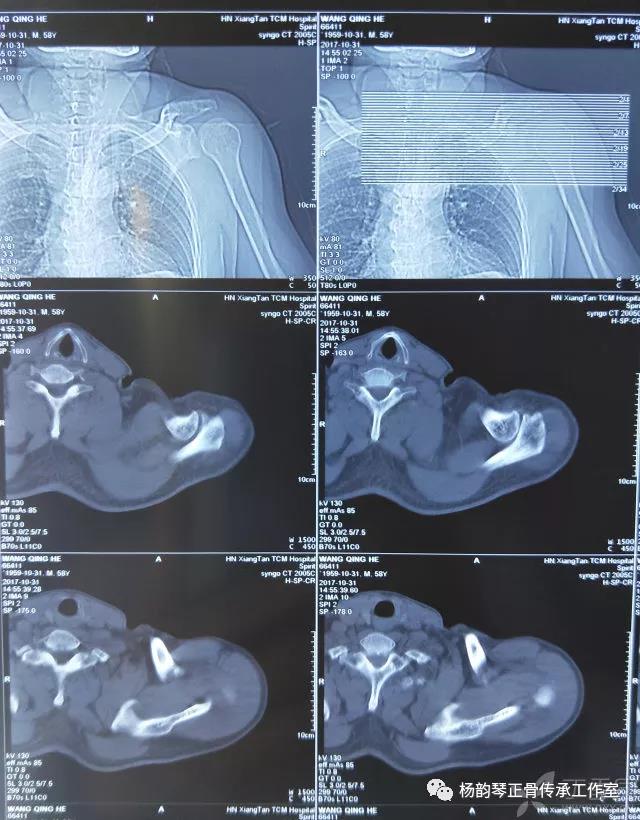

简要病史:骑摩托车跌倒致左肩部肿痛,活动受限,就诊于当地医院,拍片及磁共振检查后诊断为肩袖损伤及肩关节半脱位,予以悬吊固定,因症状缓解不明显就诊于我院。外院拍片情况如下:

应该说是一个典型的“灯泡征”影像,但是并未引起注意。

当地接诊医生应该说还是很负责的,同时拍了健侧片对比:

影像科报告,骨科医生光看报告行吗?

磁共振检查也完善了,还是报了个肩关节半脱位……影像科已经把坑挖好了……

接诊医生直接跳坑里了

就诊我院后完善CT,诊断明确——左肩关节后脱位: